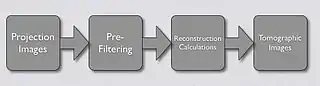

- Image quality can be improved substantially using a modified form of back-projection called Filtered Back Projection (FBP). In this technique - see Figure 7.13 - projection data is first filtered spatially to account for the effect of sudden density changes which cause the streaking in simple back-projection. The filter is referred to as a convolution filter or kernel. The procedure can be performed in the spatial frequency domain using Fourier Transform (FT) methods or directly with spatial domain processing. After the convolution process, the data for each projection is inverse Fourier transformed before the back projection computation is undertaken. In practice the task of image reconstruction is performed using special array processors and dedicated hardware, which aids in speeding up the reconstruction task.

- The overall FBP process is illustrated in the following diagram: